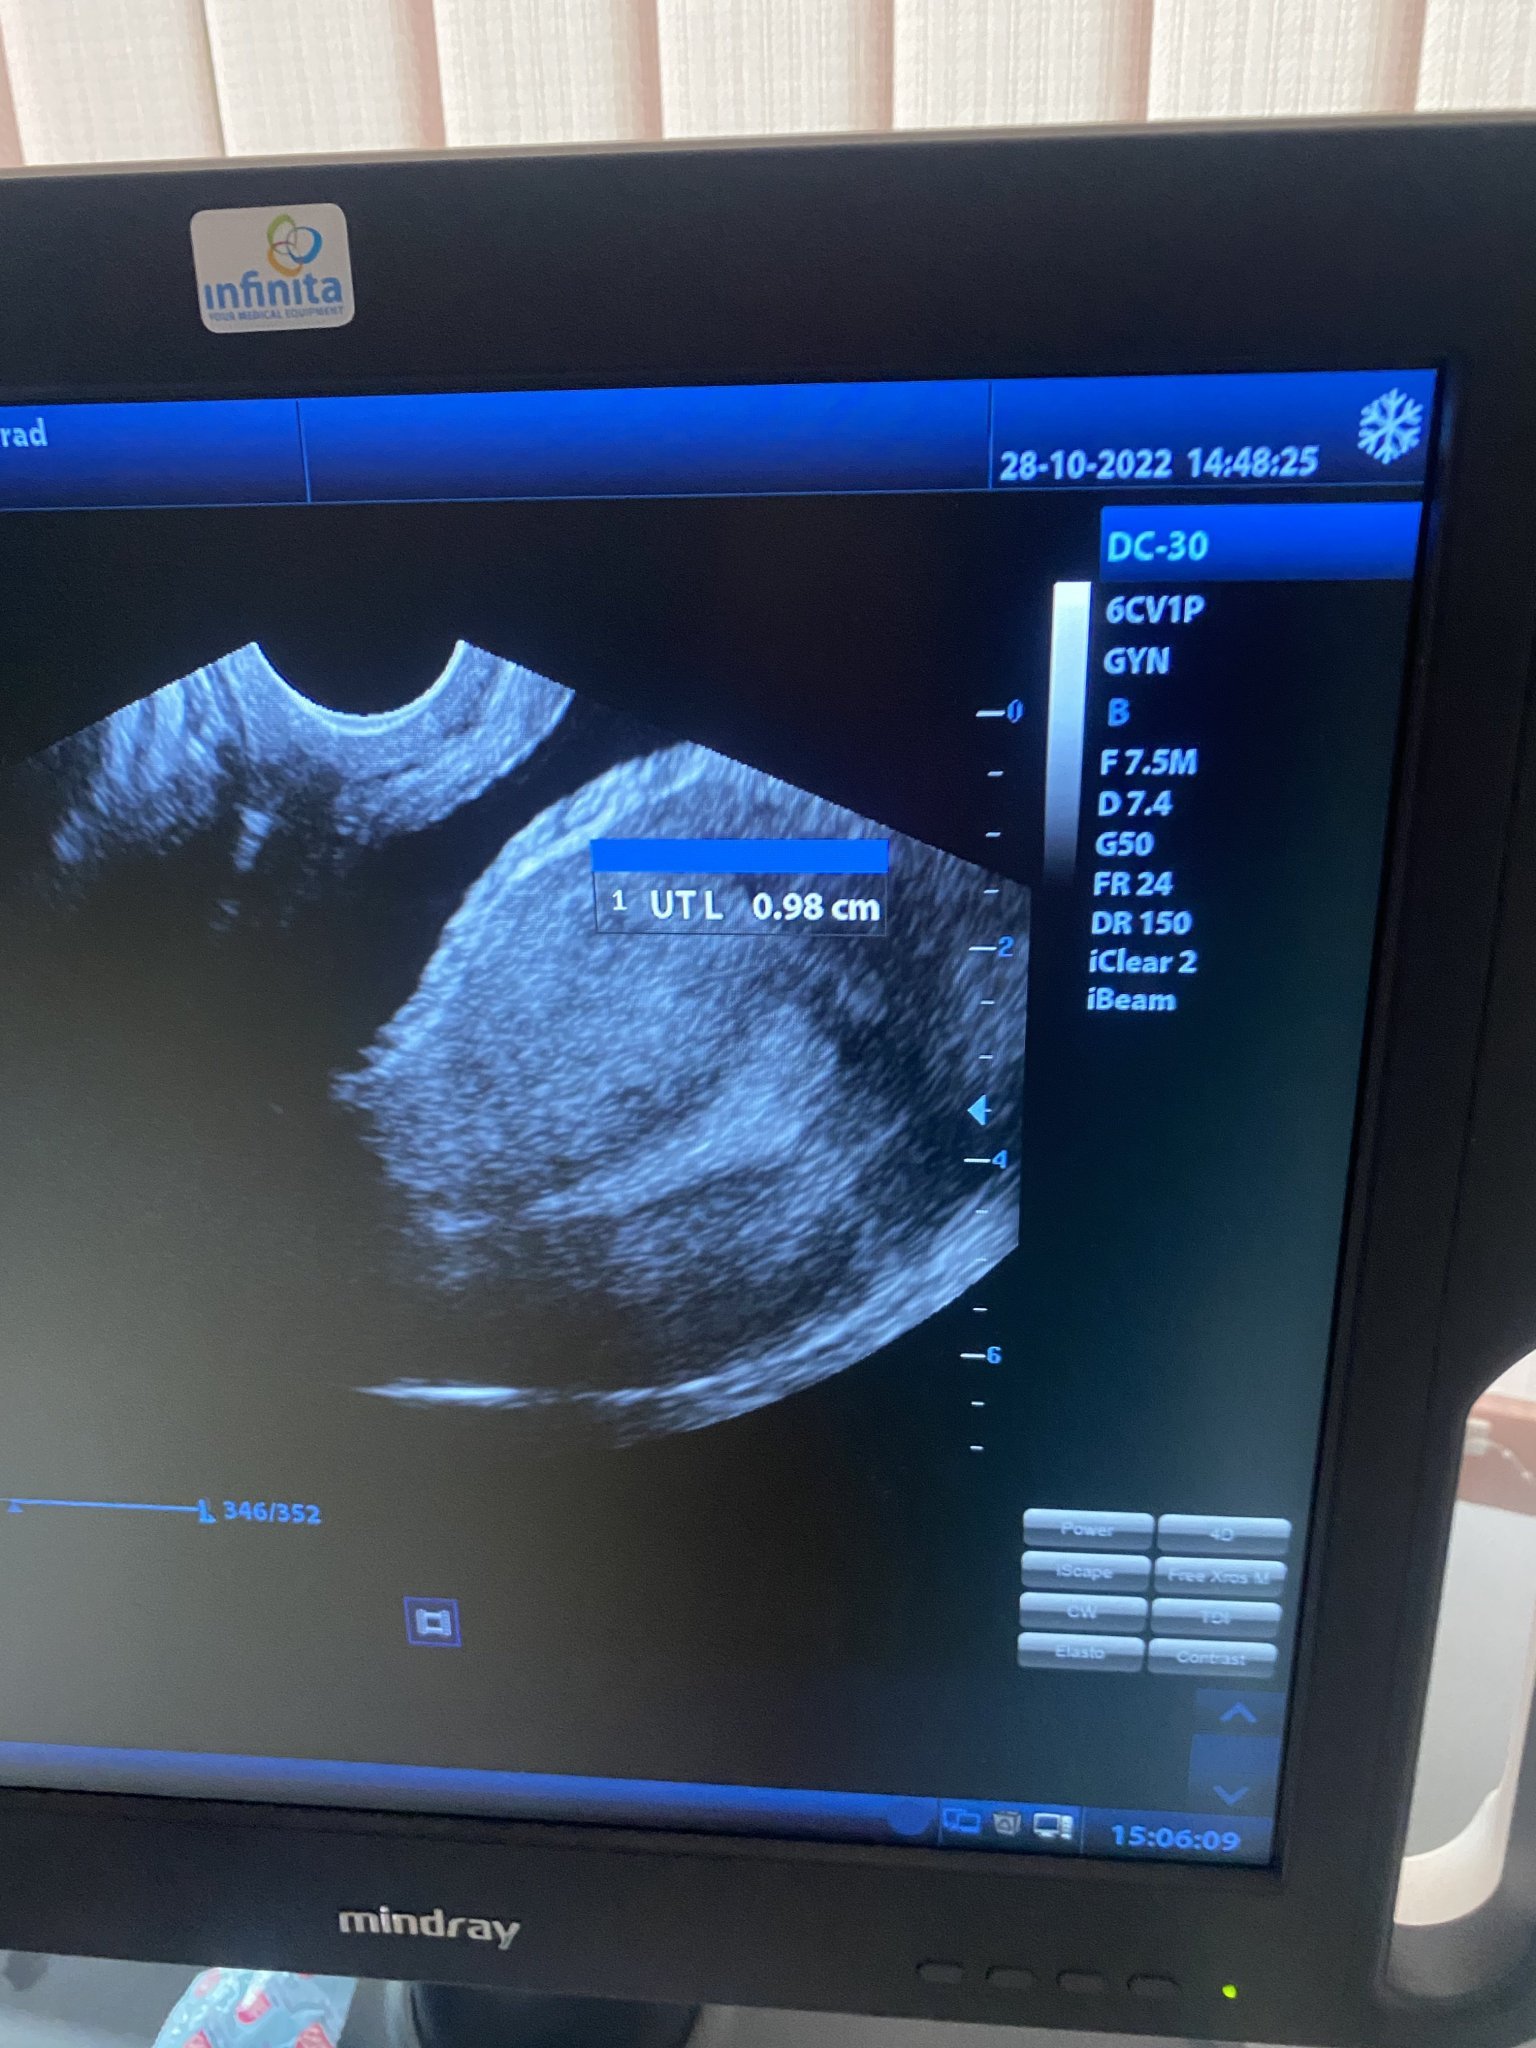

Здравейте вече нямам цикъл 43 дни но и ендометриума мие доста удебелен 0.98 мм

И докторката каза че това е предтекст за бременност но с късна овулация и можело да не се види още плода на друк случвало ли му се е да има отрицателен тест и в последствие да е бременна  странно имам две бременности без броблем

И две несполучливи на втората бременност тестовете ми бяха отрицателни а на ехограф се видя сак без ембрион

Не мога да преценя какво става

Чхг правихте ли. На колко години сте. Защото аз виждам сакче. Но е трудно забележимо.